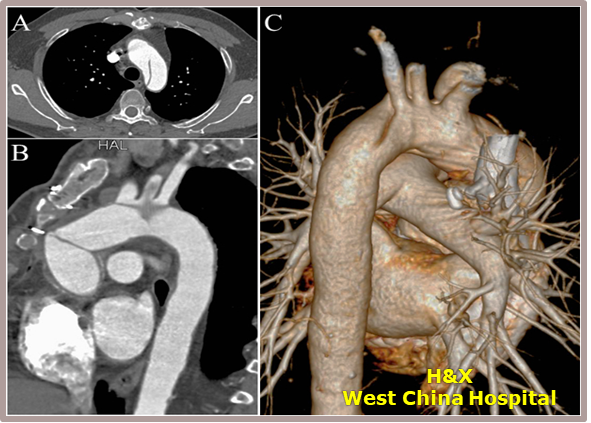

★ Case 2

男性,50岁,胸痛7+小时;

既往史:既往诊断高血压,未规律服药及监测血压;

个人史:吸烟30余年,日均20支;

夹层动脉瘤CTA:A型主动脉夹层,初破口位于主动脉弓近端,逆撕至主动脉根部,左颈总动脉及左锁骨下动脉根部受累,夹层远端累及至双侧髂动脉。

术前影像

置入双分支术中支架

术后影像